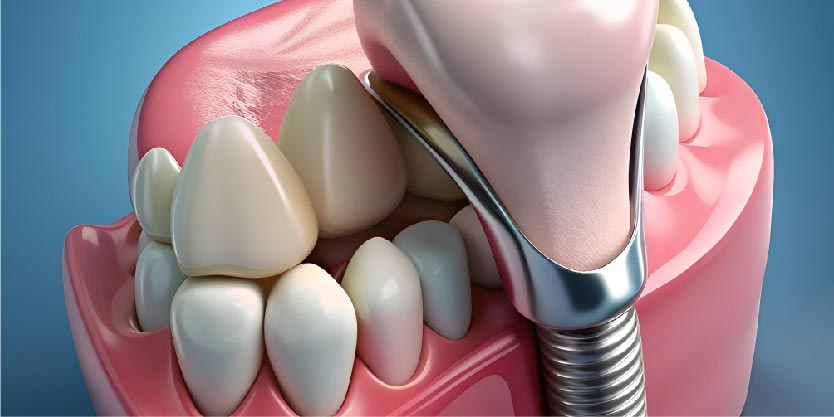

- Patients with missing teeth: Dental implants, bridges, or dentures can replace missing teeth and improve bite and aesthetics.

Dentures

Another conventional method of replacing missing teeth is dentures. An entire lost tooth arch is replaced with a set of full dentures. Multiple lost teeth in various locations are replaced with partial dentures. Your jawbone supports your dentures, which are positioned on top of your gums.

Dentures supported by implants are another option. Traditional dentures resemble these appliances. But they affix to dental implants rather than supporting your gums in this manner. This provides a great deal more stability than traditional dentures.